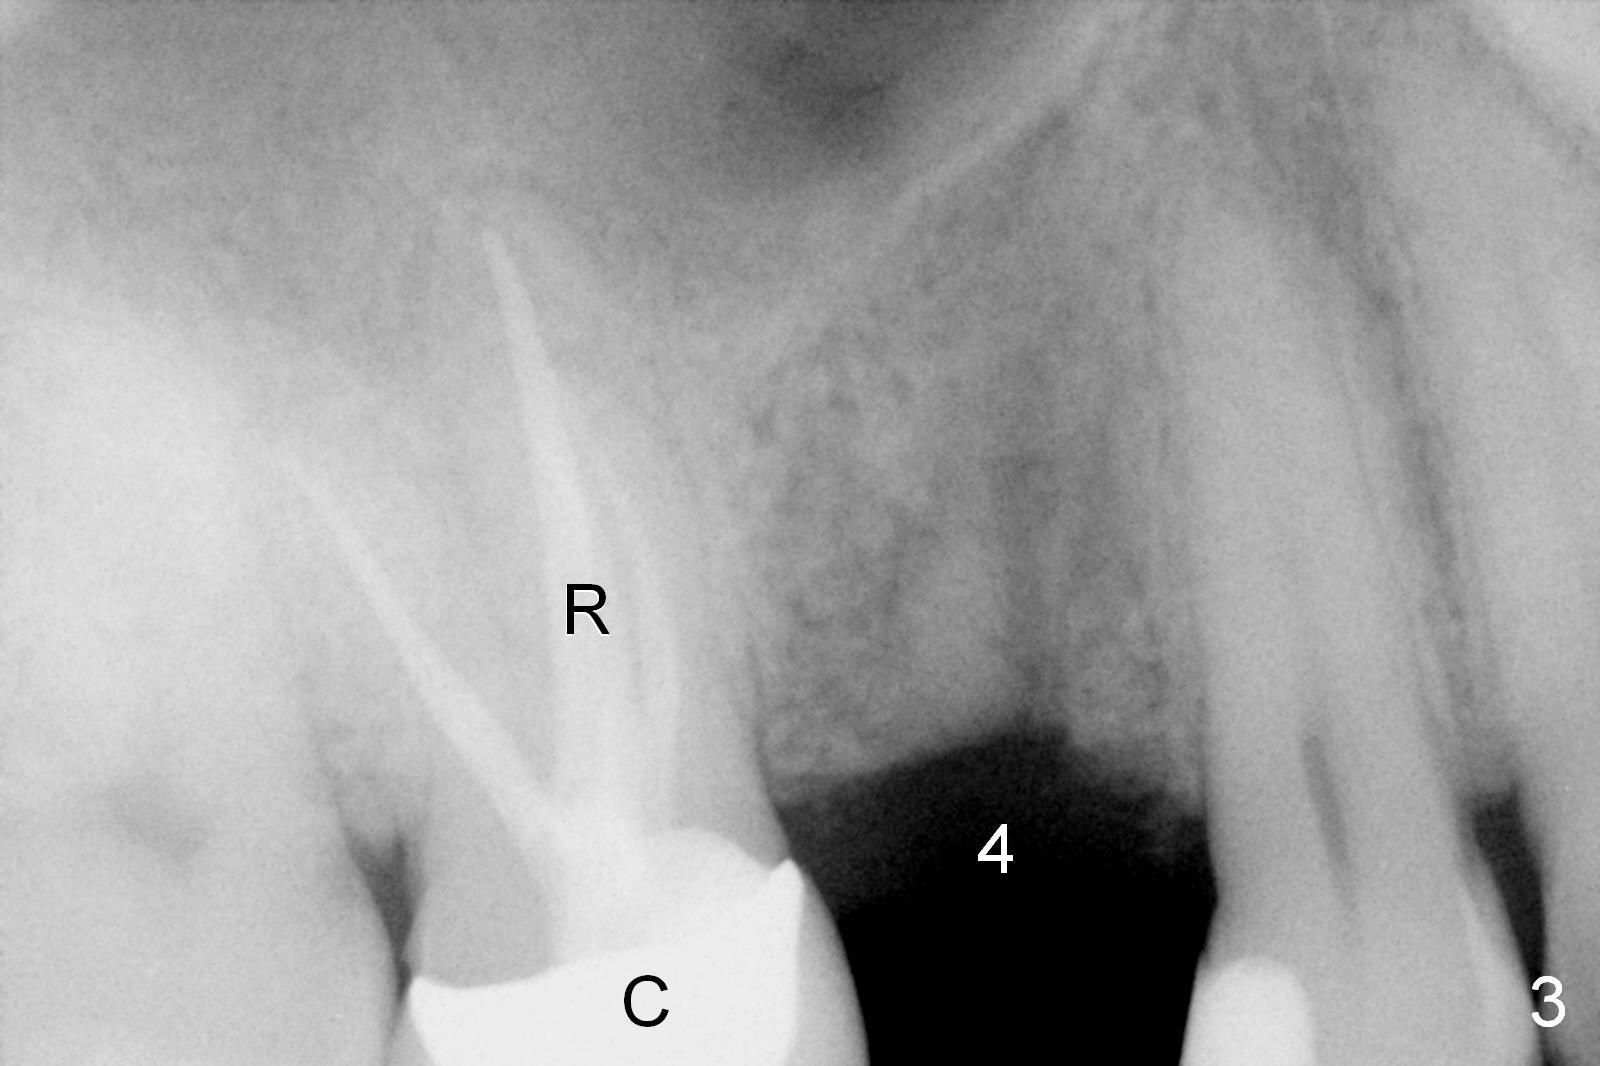

ZC is a 36-year-old man without significant medical history. His chief complaint is "I have Pain sometimes". His oral hygiene is poor (Fig.1). The tooth #3 has large MO caries with periapical radiolucency (*). The tooth #4 is non-salvageable (Fig.1,2). Four months after scaling & root planing, RCT and crown for #3 and extraction of #4 (Fig.3), a 5x8 mm Bicon implant is placed at the site of #4 (Fig.4). Peri-implant space is obliterated 5 months postop (Fig.5). The 2nd surgery is performed to uncover the implant and to place a temporary abutment. Two weeks later, a 5.0x.3.0 mm 0 degree Stealth Abutment 3.0 mm Post is placed (Fig.6). The most recent recall PA shows no bone loss for 5 years 3 months post cementation (Fig.7).